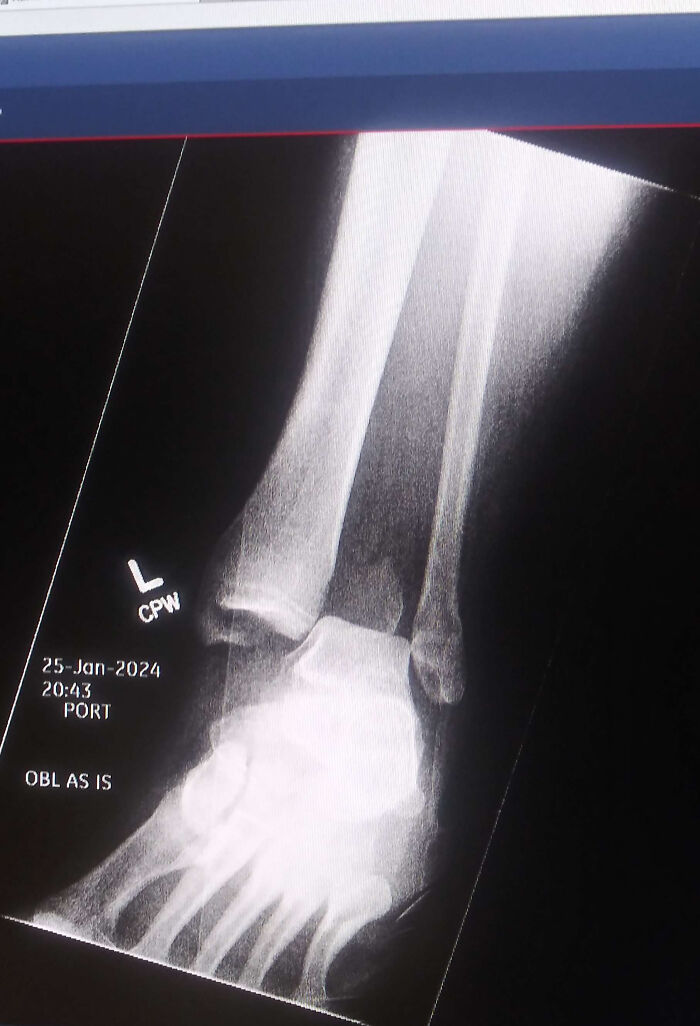

Poważnie skręcona kostka — przypadek do nauki